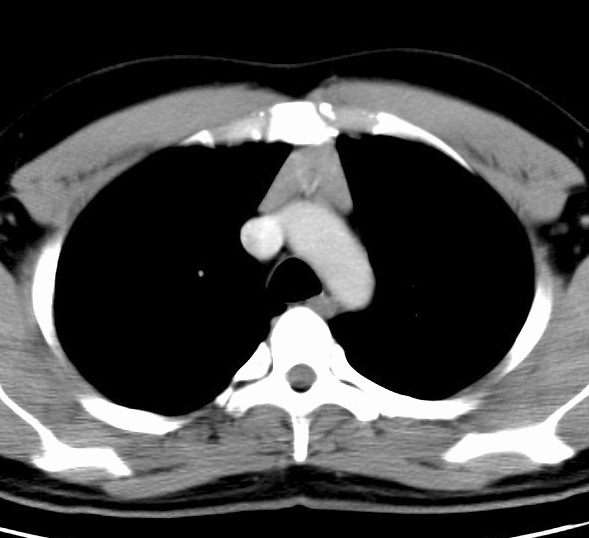

Thymic hyperplasia